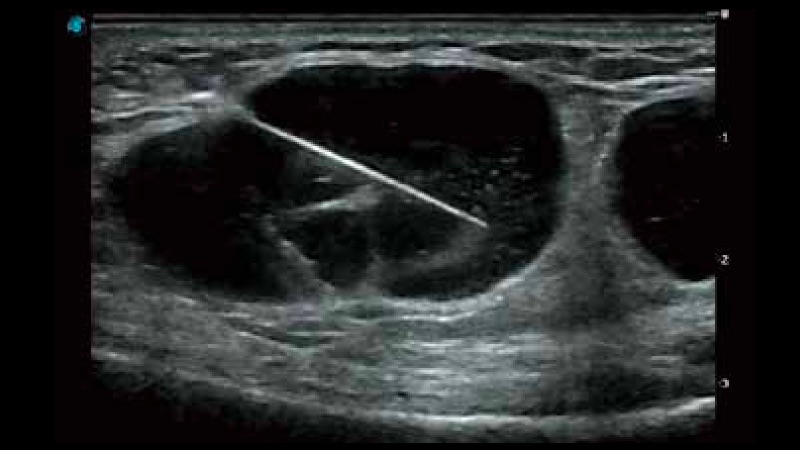

复合材料线阵探头

凭借狗万官方网站先进的成像技术和优异的探头技术提供的清晰的图像表现,您可以更自信地做出临床决策。